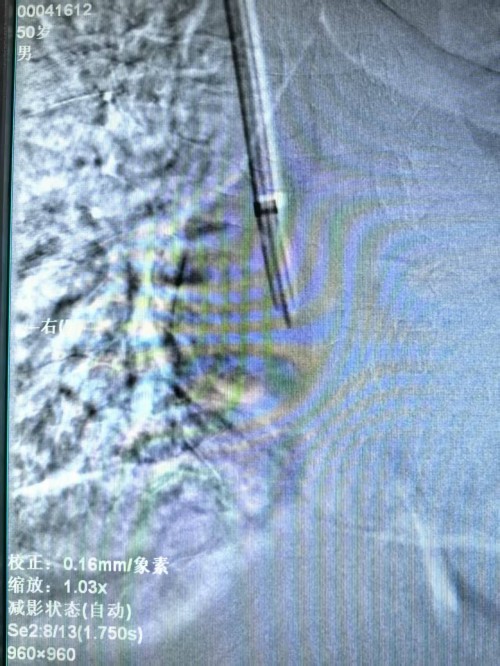

该项手术由医院安宁疗护一科曲伟主任主刀,术前仔细评估患者一般情况及血管情况,制定手术方案,手术全程在导管室进行,术中实时监测血流动力学指标,超声引导下通过精准的静脉解剖定位置入导管,术中X线定位下将导管撕脱鞘送入颈内静脉至上腔静脉-右心房交界处,位置满意后予以固定。